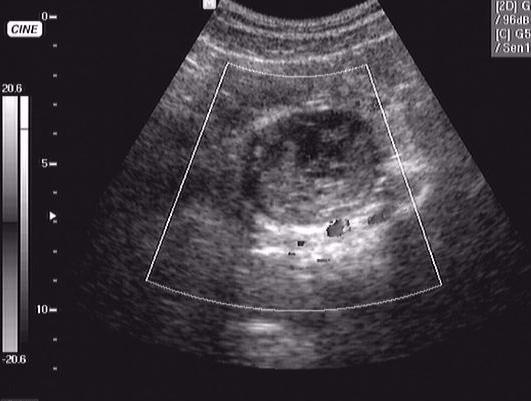

кровоизлияние в кисту яичника

девушка 16 лет, дисменоррея. поступила в хирургию вчера вечером д-з о. аппендицит.